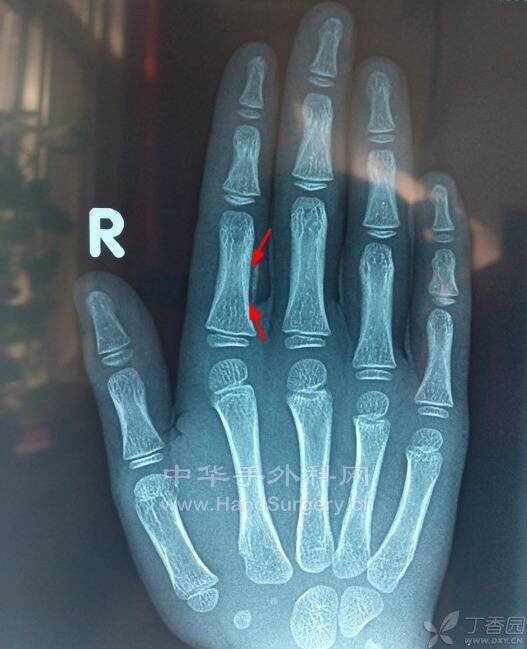

src=http___img.dxycdn.com_upload_2014_11_08_43_12286145.snap.jpg&refer=http___im.jpg

丁香园上的图片,像什么

病房有一个类似的病人

今天手术一个类似的病历

IMG_20210909_093659.jpg

IMG_20210909_093716.jpg

IMG_20210909_093842.jpg